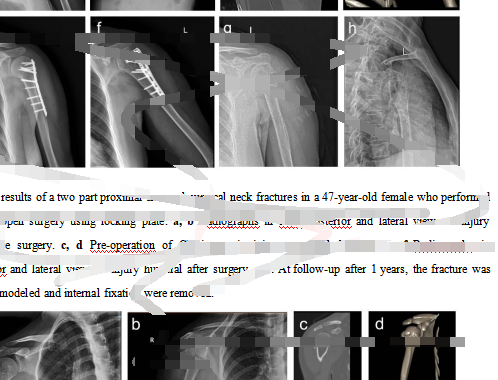

在另一家“論文工廠”,當記者表示著急想發醫學方面頂級期刊,對方推薦給記者一篇已基本寫好的頸部骨科研究英文論文,并發來部分內容供記者審核評閱,總“標價”3.75萬元。

“論文工廠”發給記者的一篇已基本寫好的頸部骨科研究英文論文的部分內容